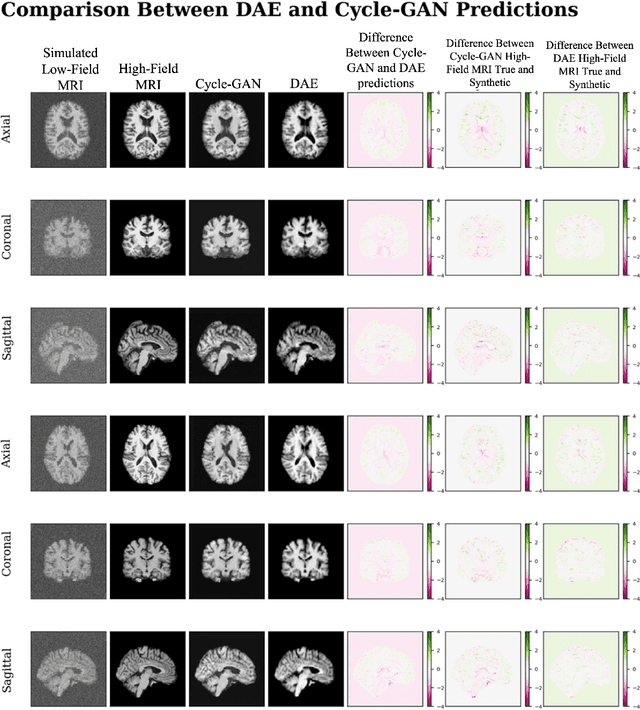

In this work, a denoising Cycle-GAN (Cycle Consistent Generative Adversarial Network) is implemented to yield high-field, high resolution, high signal-to-noise ratio (SNR) Magnetic Resonance Imaging (MRI) images from simulated low-field, low resolution, low SNR MRI images. Resampling and additive Rician noise were used to simulate low-field MRI. Images were utilized to train a Denoising Autoencoder (DAE) and a Cycle-GAN, with paired and unpaired cases. Both networks were evaluated using SSIM and PSNR image quality metrics. This work demonstrates the use of a generative deep learning model that can outperform classical DAEs to improve low-field MRI images and does not require image pairs.